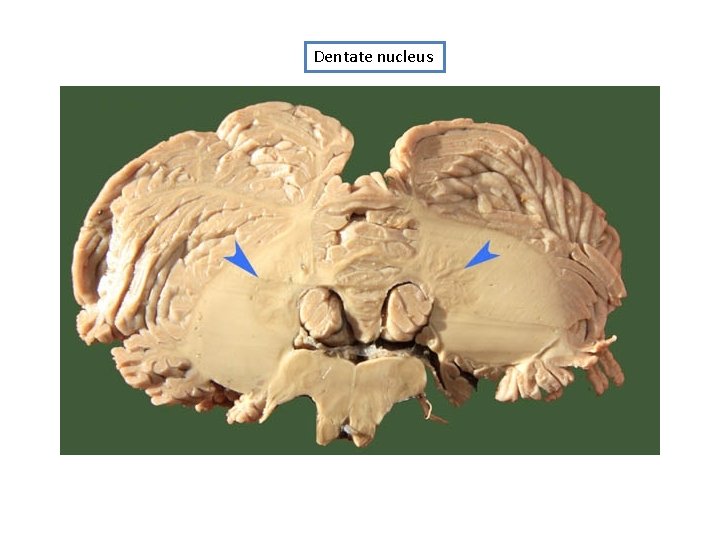

Dentate nucleus

Superior cerebellar peduncle